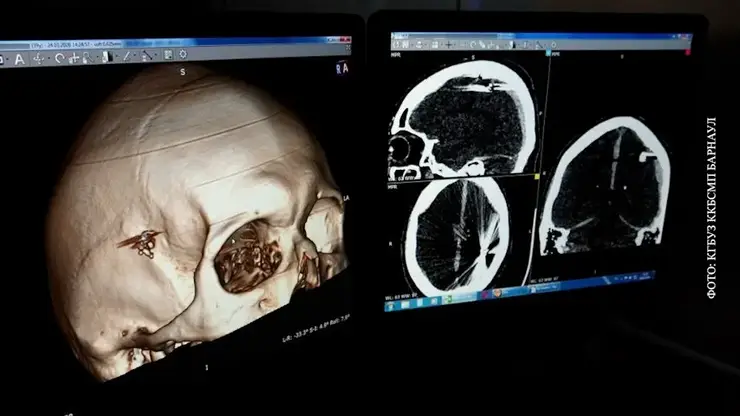

Обследование показало: пуля раздробила кости черепа, а осколки проникли в мозг. Операция по их извлечению длилась около 2,5 часа. Хирурги удалили инородные фрагменты, устранили гематому и стабилизировали состояние пациента.